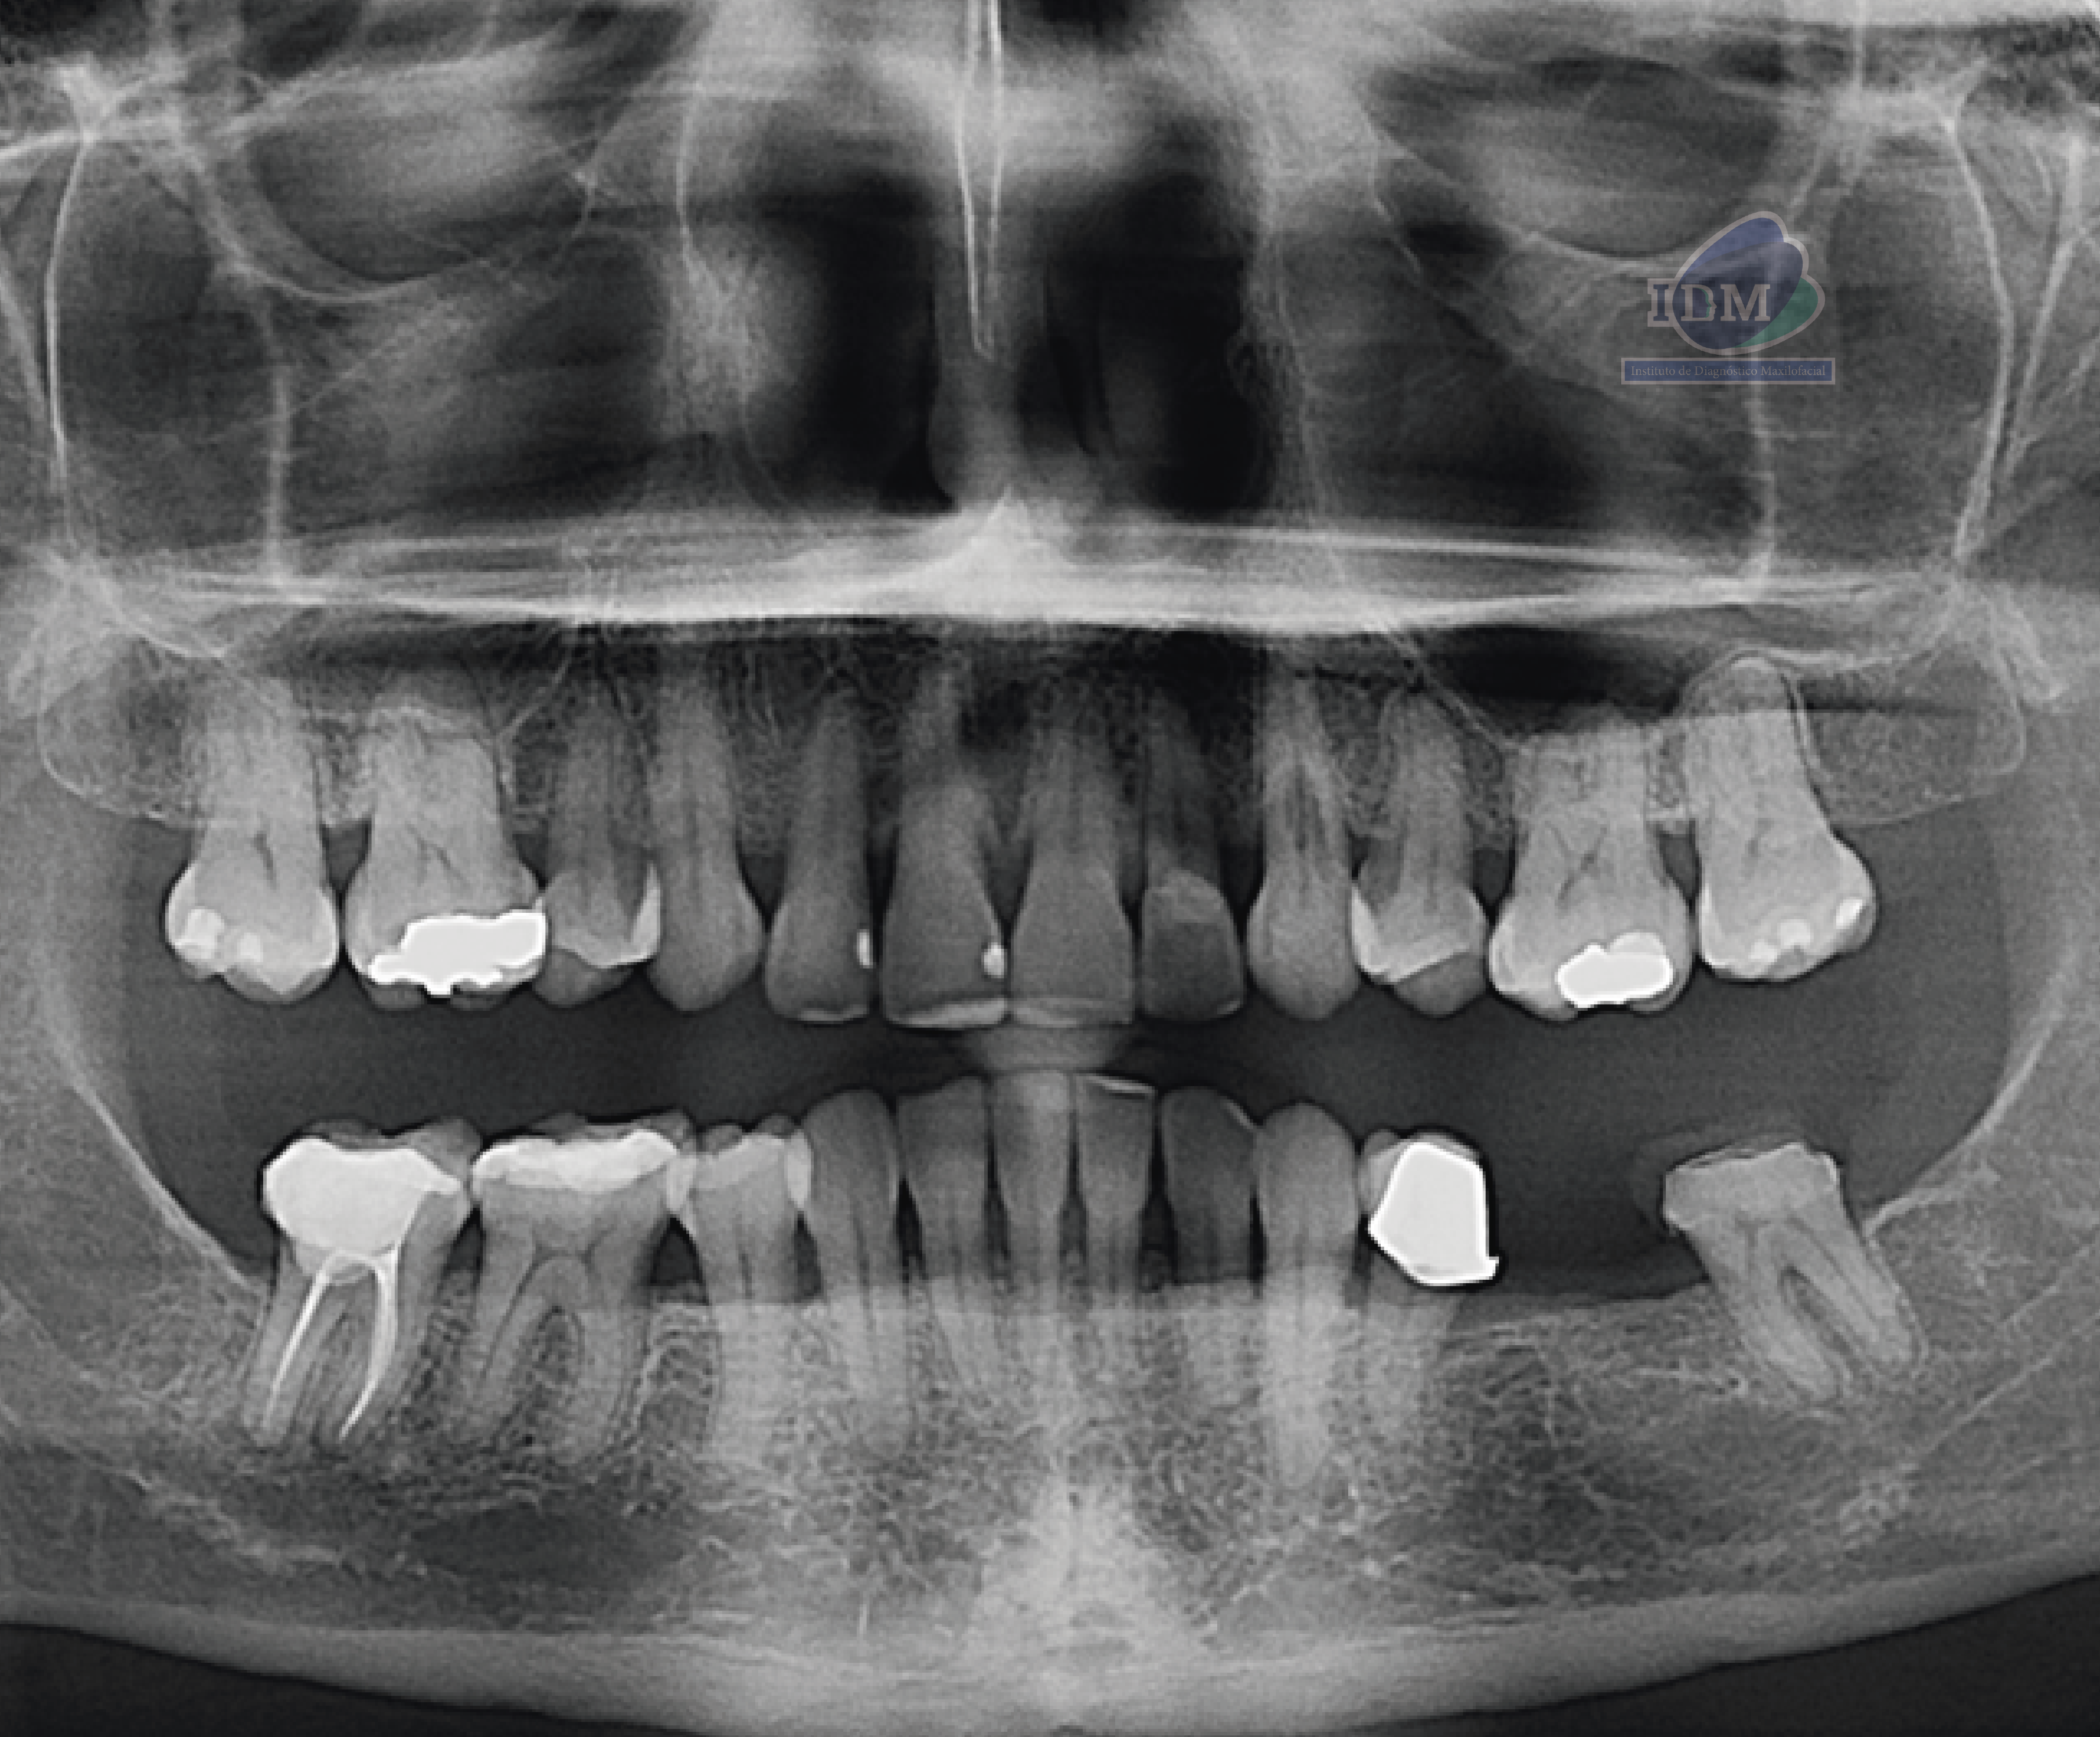

Radiografia Panorámica

En la radiografía panorámica se evidencian múltiples restauraciones coronarias, así como tratamiento de conductos en la pieza 47. En la pieza 23 se aprecia una disminución de la densidad radicular en la región cervical.